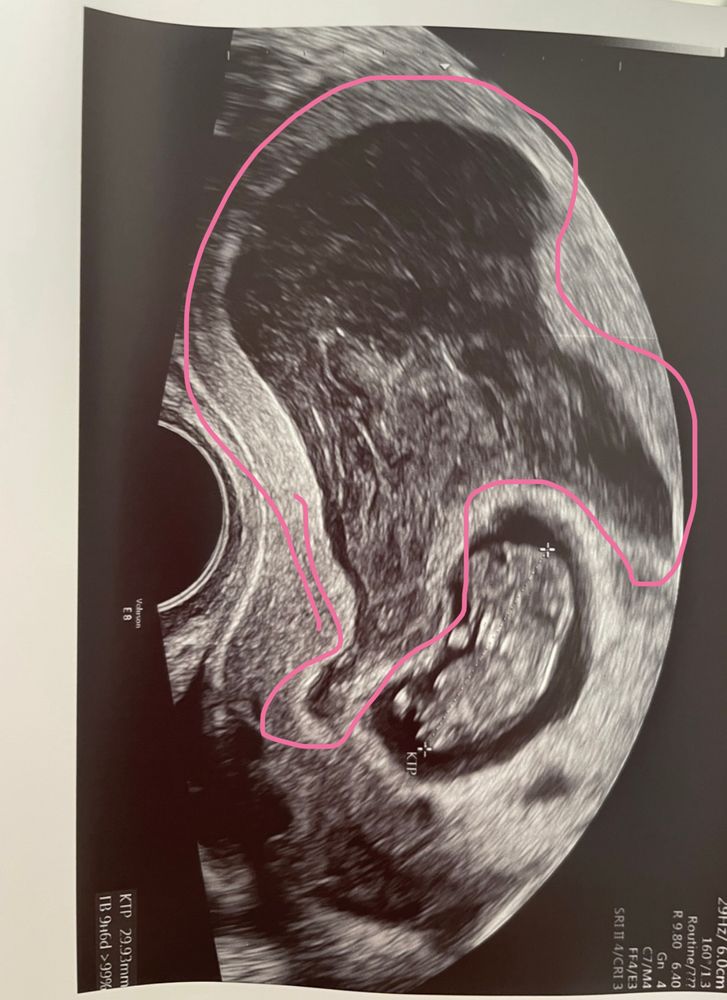

Гематома 2 триместр

Гематома 2 триместр 114 фото